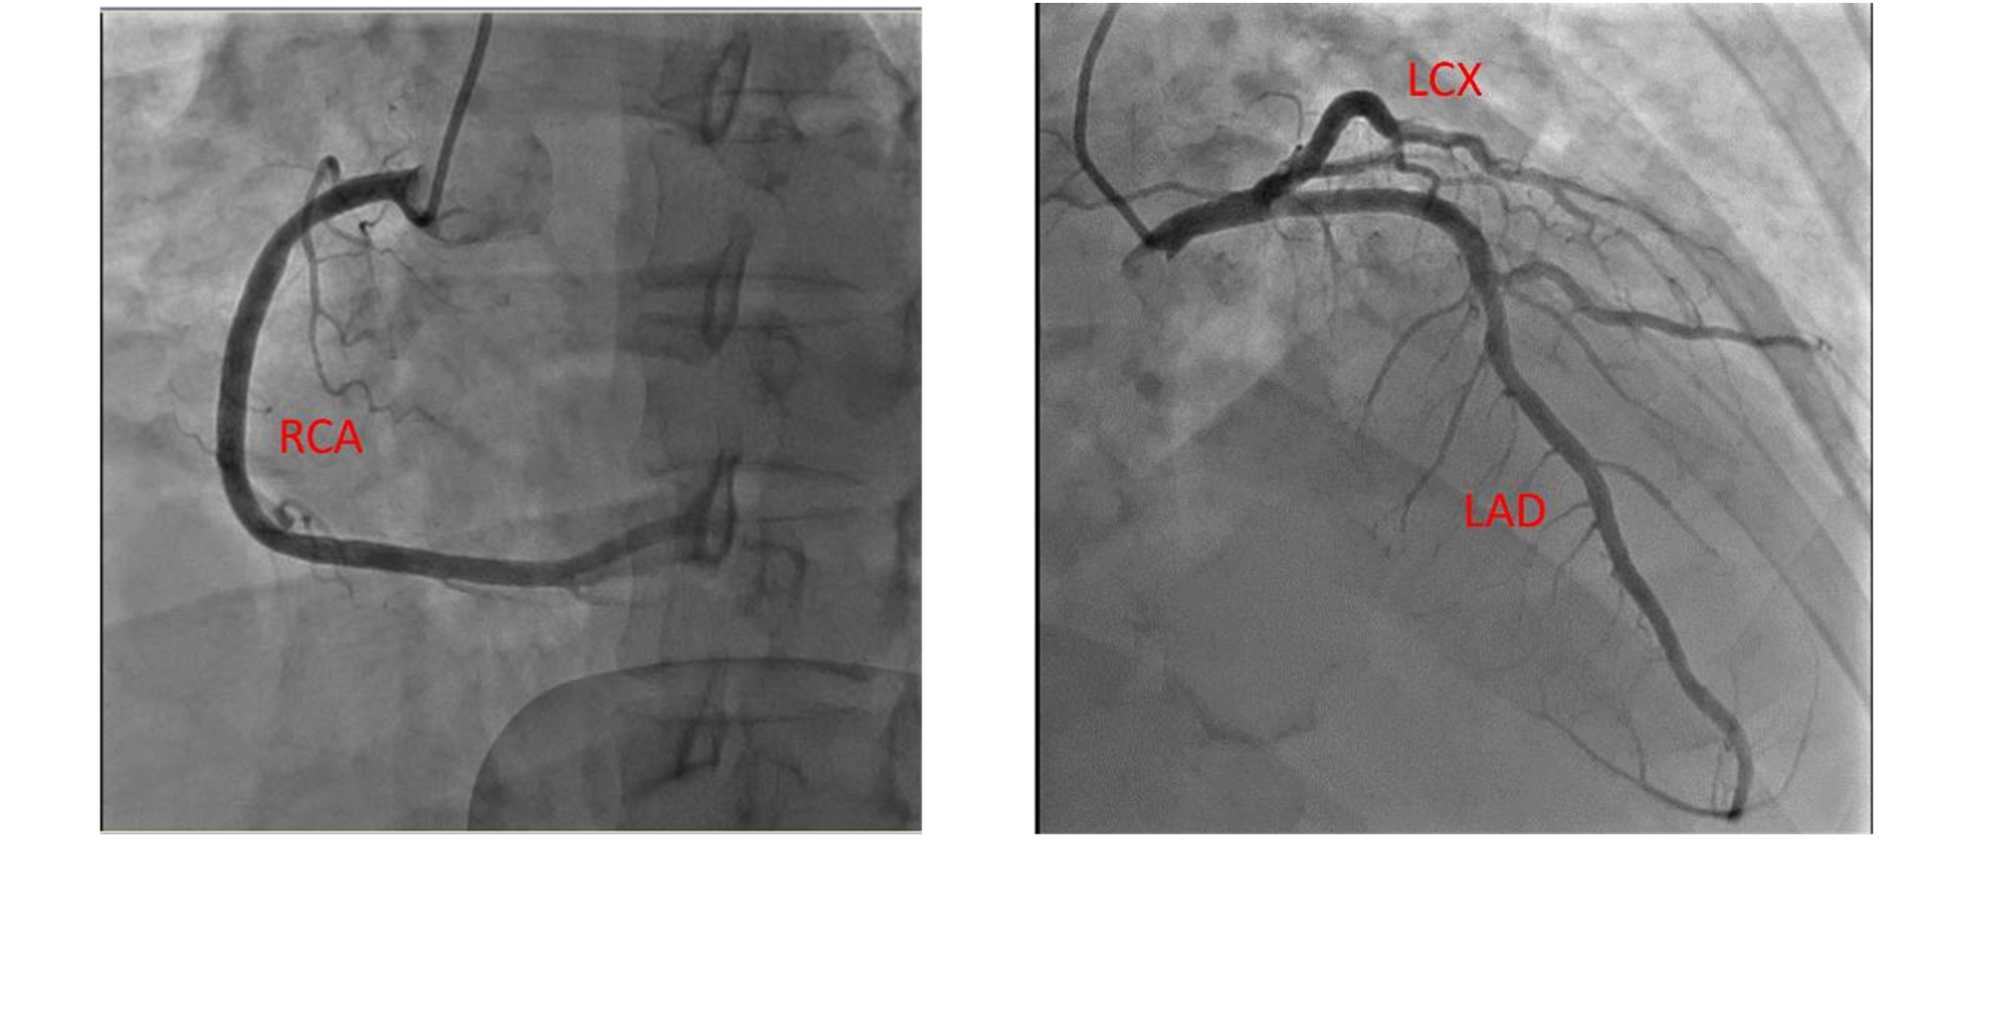

到达我院急诊后完善心电图示:窦性心律,Ⅰ、aVL导联及V2~V6导联ST段抬高,T波倒置(见图2(A)),诊断为“急性ST段抬高型心肌梗死”。行急诊冠状动脉造影:LM:未见明显狭窄,TIMI血流3级,LAD:中段可见斑块,余未见明显狭窄,TIMI血流3级,LCX:未见明显狭窄,TIMI血流3级,RCA:未见明显狭窄,TIMI血流3级(见图3)。为进一步治疗收住院。入院后诊断:急性ST段抬高型心

注:LM:未见明显狭窄,TIMI血流3级,LAD:中段可见斑块,余未见明显狭窄,TIMI血流3级,LCX:未见明显狭窄,TIMI而流3级,RCA:未见明显狭窄,TIMI而流3级。

Figure 3. Emergency coronary angiography

3. 急诊冠脉造影结果